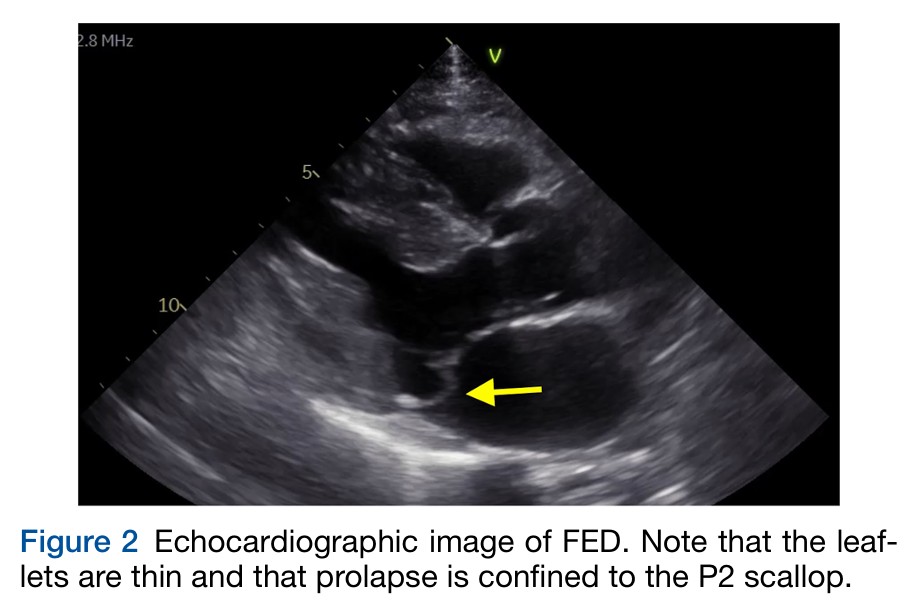

A deficiência fibroelástica, por sua vez, é caracterizada por folhetos e cordoalhas afiladas e com o prolapso tipicamente restrito ao segmento P2 do folheto posterior. É verdade, porém, que, na presença de regurgitação mitral, o maior estresse parietal (pelo aumento da velocidade) pode induzir alterações nos folhetos com superposição de tecido fibroso levando a espessamento focal.